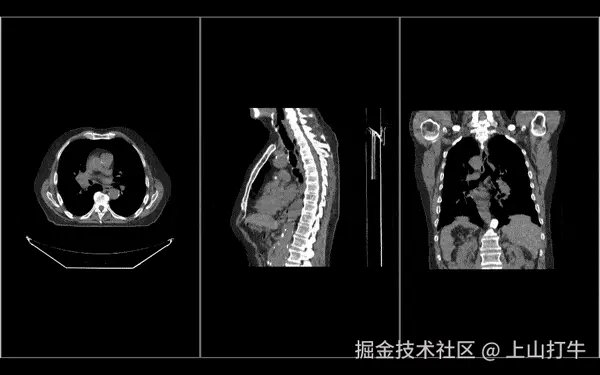

渲染

使用新的渲染引擎及其 Stack(二维序列)Volume(三维体数据) 视口

• 以不同方向(如轴向、矢状和冠状面)查看同一卷,而无需再次重新加载整个卷(最小内存占用)